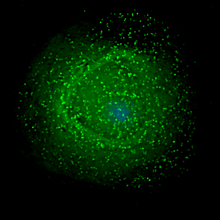

Scanning electron micrograph of HIV-1 (in green) budding from cultured lymphocyte. Multiple round bumps on cell surface represent sites of assembly and budding of virions.

HIV assembling on the surface of an infected macrophage.